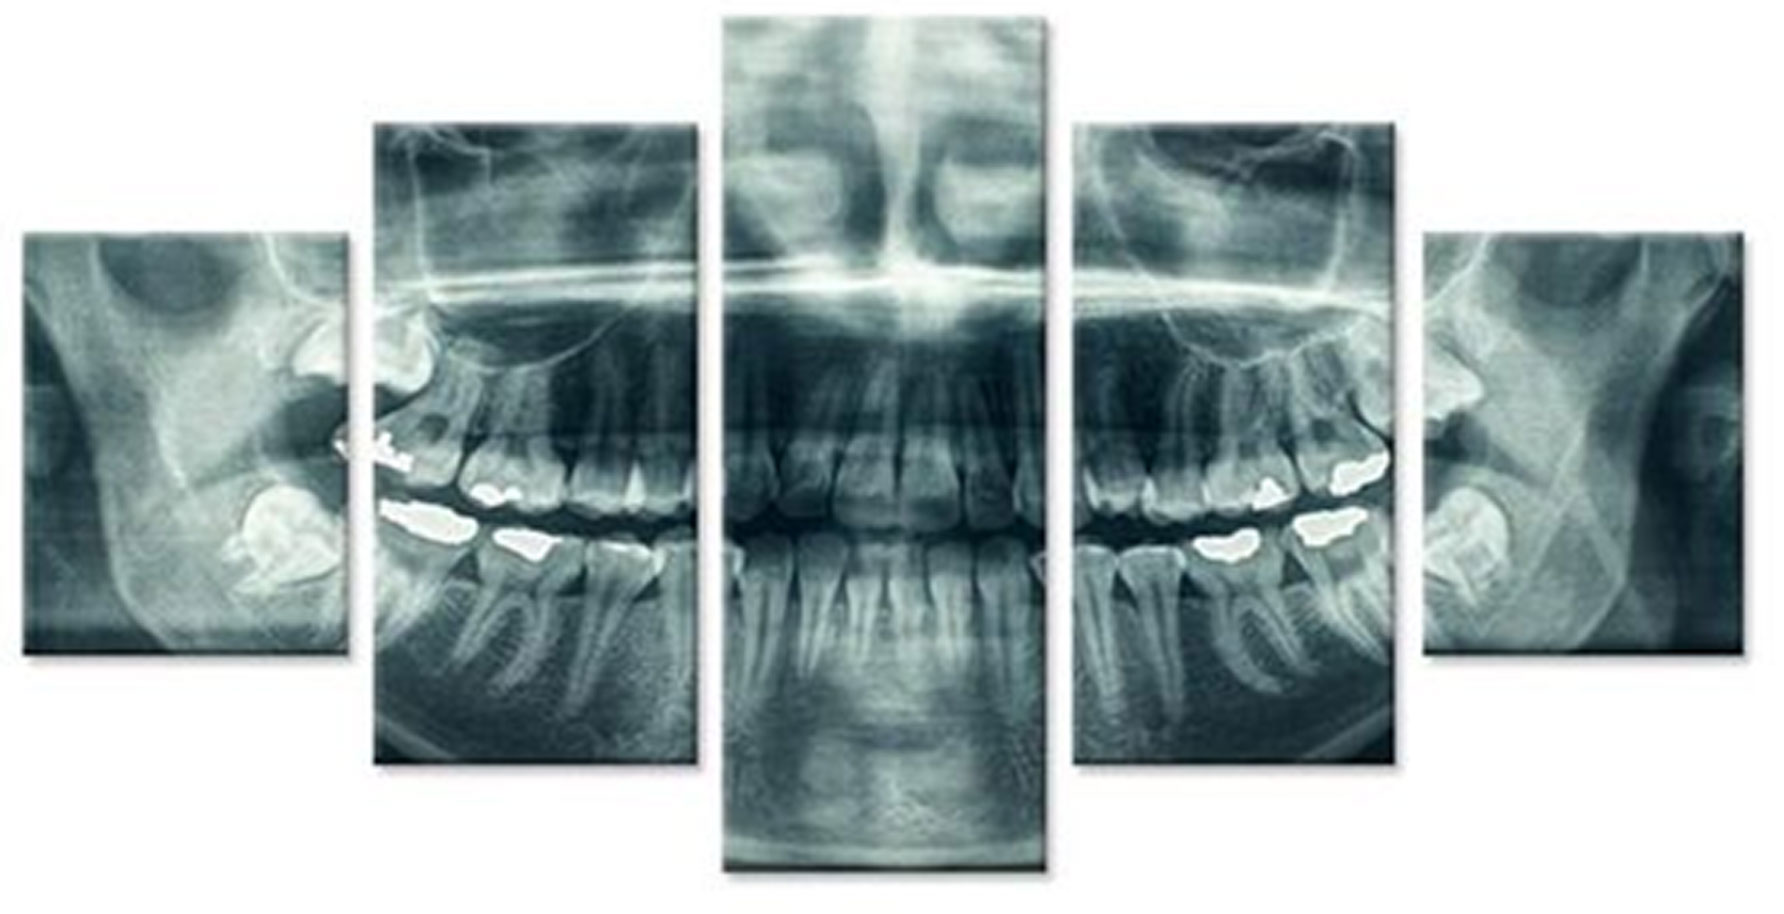

For an exact diagnosis and a target-oriented treatment it is necessary to look inside the tooth. EDG offers wide range of 2D and 3D CBCT Digital Radiography.

We use the newest technology to enable a precise treatment for our patients through imaging methods.